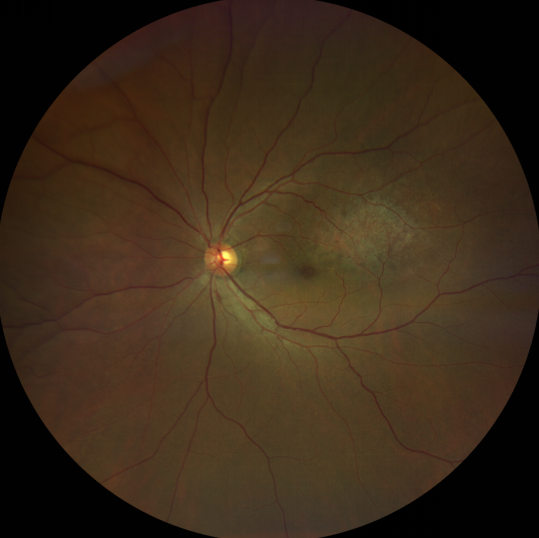

脈絡(luò)膜黑色素瘤是成年人常見的眼內(nèi)惡性腫瘤,其患病率在我國居眼內(nèi)惡性腫瘤的第二位,僅次于視網(wǎng)膜母細(xì)胞瘤。其惡性程度高,不僅可致患者喪失視力,而且嚴(yán)重威脅患者生命,即使在沒有明確轉(zhuǎn)移前摘除患眼眼球,其5年死亡率也有17%-53%。

脈絡(luò)膜黑色素瘤是葡萄膜惡性腫瘤中較多的一種。葡萄膜腫瘤主要發(fā)生于脈絡(luò)膜、睫狀體和虹膜。其中,脈絡(luò)膜腫瘤占80%,睫狀體腫瘤占12%,虹膜腫瘤占8%。惡性程度高的腫瘤主要發(fā)生于脈絡(luò)膜。發(fā)生于睫狀體的腫瘤惡性程度偏低,發(fā)生于虹膜的腫瘤多數(shù)為良性。脈絡(luò)膜黑色素瘤的特點(diǎn)是惡性程度高、易侵襲轉(zhuǎn)移、預(yù)后極差,嚴(yán)重威脅患者的視力和生命。其發(fā)病率有種族差異性,以高加索及白種人居多,黑人發(fā)病率低,亞洲人居于中間。

脈絡(luò)膜黑色素瘤患者在發(fā)病早期無眼痛等癥狀,當(dāng)腫瘤較小時(shí)較難發(fā)現(xiàn),隨著病程進(jìn)展,腫瘤增大,發(fā)生滲出性視網(wǎng)膜脫離或累及黃斑,視力下降才就診。

脈絡(luò)膜黑色素瘤惡性程度高,50%的患者會(huì)發(fā)生轉(zhuǎn)移,轉(zhuǎn)移到肝、肺等遠(yuǎn)處臟器,常見的轉(zhuǎn)移方式是經(jīng)鞏膜導(dǎo)管擴(kuò)散,經(jīng)視神經(jīng)蔓延者罕見。一旦發(fā)生轉(zhuǎn)移,1年生存率只有10%,即絕大多數(shù)病人在半年至1年間會(huì)失去生命。因此,早期診斷和選擇合適的治療方式對(duì)有效提高局部腫瘤的控制率、降低腫瘤的遠(yuǎn)處轉(zhuǎn)移率、延長患者的生存率具有重要意義。